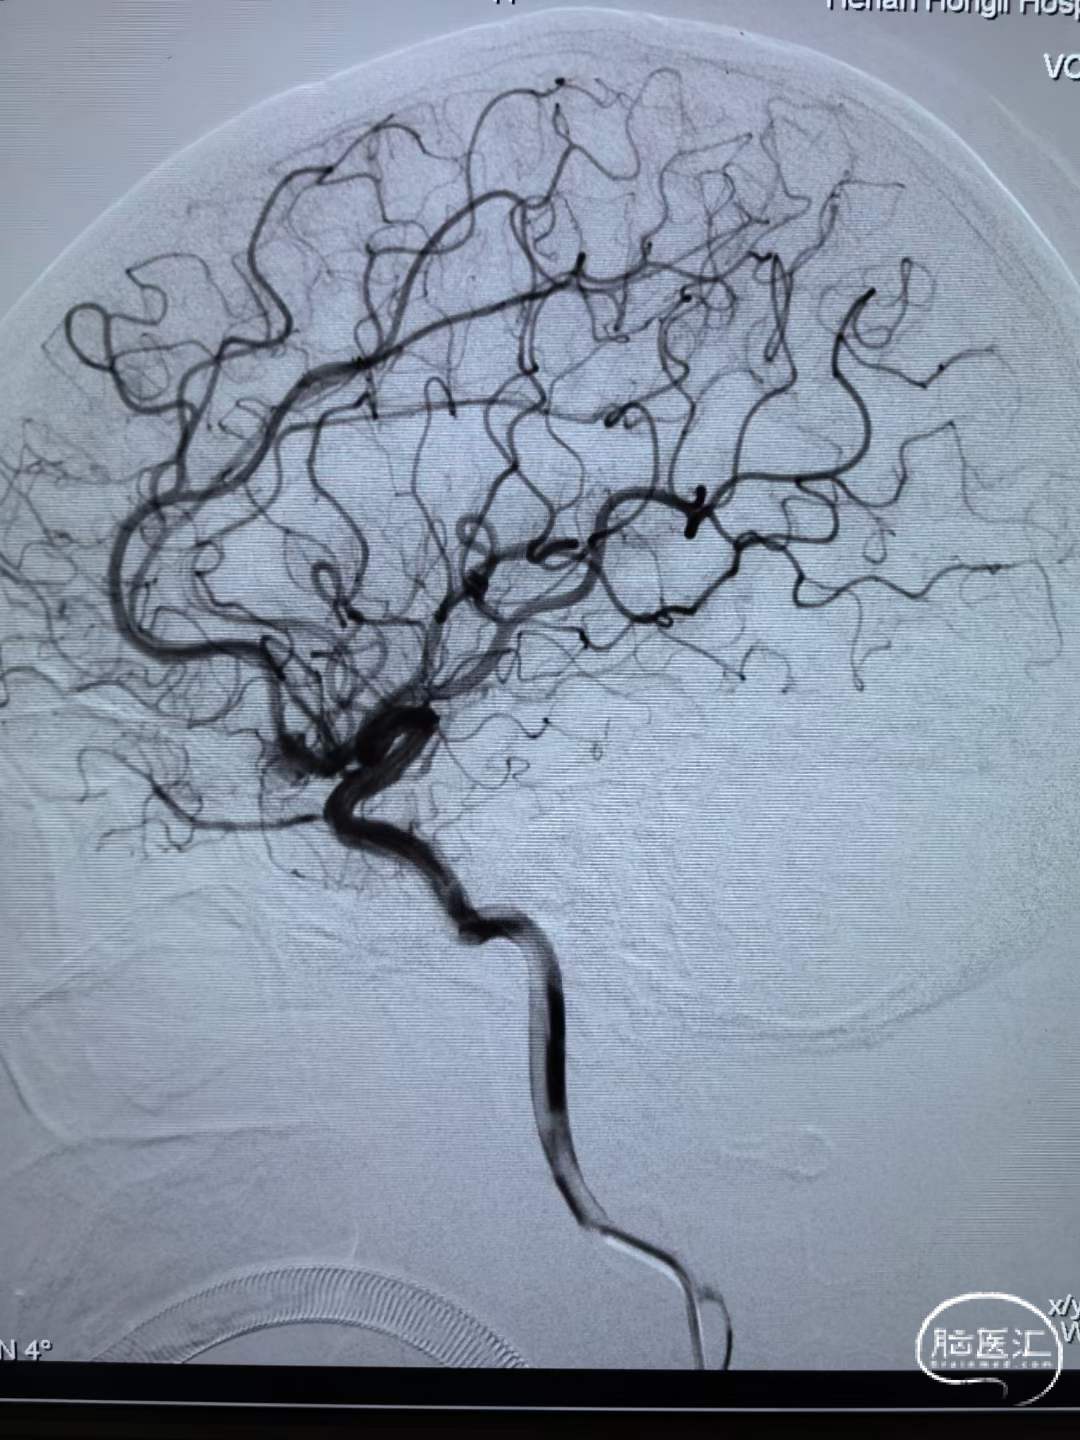

连续填塞五个弹簧圈致密栓塞动脉瘤,植入支架覆盖瘤颈。